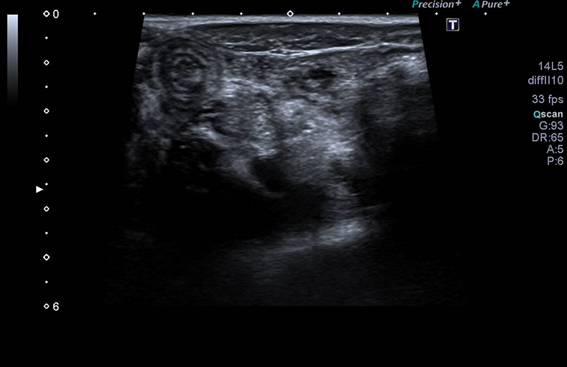

En la ecografía se hallan ganglios reactivos en fosa ilíaca derecha e invaginación ileo-ileal con imagen en diana, resuelta de forma espontánea mediante la compresión de la sonda ecográfica, confirmando el diagnóstico de adenitis mesentérica con invaginación intestinal secundaria.